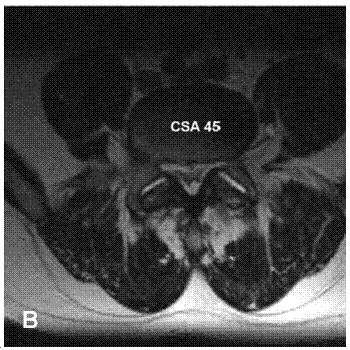

La resonancia magnética es el examen de eleccion.